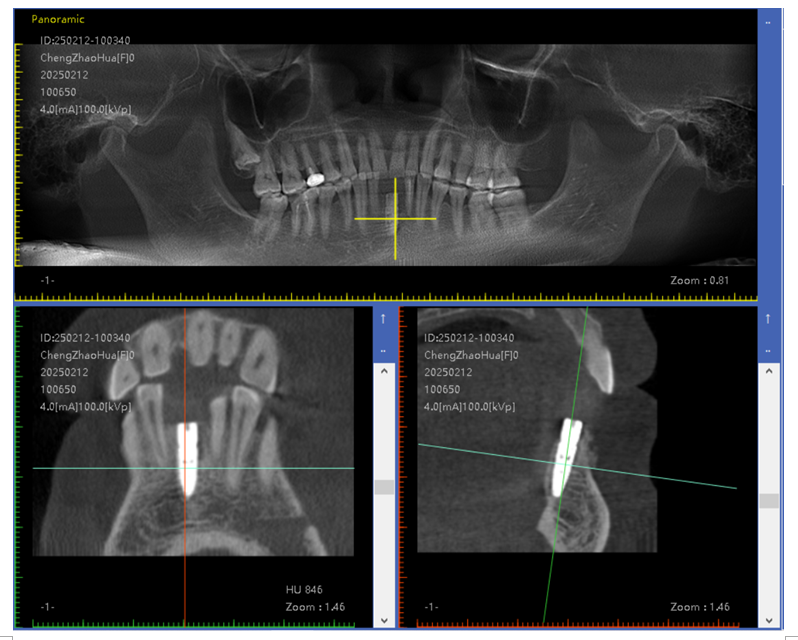

数字化导板技术:通过口腔 CT 扫描获取患者口腔颌骨的精确三维数据,利用计算机辅助设计(CAD)和计算机辅助制造(CAM)技术制作出个性化的手术导板。在牙槽外科手术中,如拔牙、种植牙等,导板可以精确引导手术器械的操作,提高手术的准确性和可预测性,减少手术创伤和并发症,同时缩短手术时间。

即刻种植与即刻修复技术:在拔牙后立即将种植体植入拔牙窝内,并在种植体植入后短期内(通常在数天至数周内)完成牙冠修复。这种技术可以减少患者缺牙的时间,避免牙槽骨因缺牙而发生吸收,同时能够更快地恢复患者的咀嚼功能和美观。